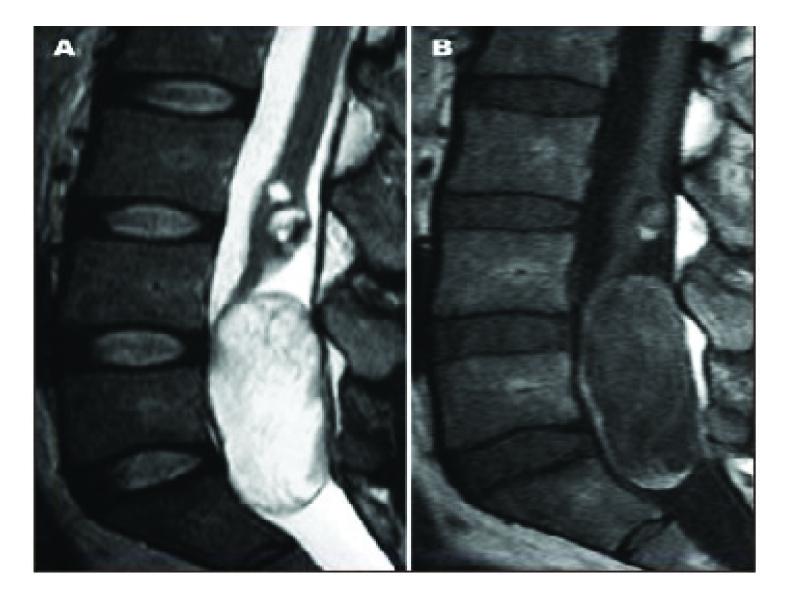

Intradural extramedullary epidermoid (EC) cysts are uncommon (0.2-1%). Acquired tumors appear more frequently as a late complication of lumbar punctures (40%). The authors present three cases of epidermoid cysts of the cauda equina which were surgically treated in their department during the past five years. All three had suffered lumbar punctures for rachianesthesia 6-9 years prior to their presentation. The patients' ages ranged between 19 and 31. Surgical treatment was deemed necessary because of the space-occupying nature of this slow-growing lesion, and this indication was supported by the MRI findings. Two-level laminectomy and microsurgical total tumor ablation were performed in all three cases. There were no postoperative complications.

硬脊膜内髓外表皮样囊肿(EC)较为罕见(0.2%-1%)。后天性肿瘤更常作为腰椎穿刺的晚期并发症出现(40%)。作者介绍了过去五年在其科室接受手术治疗的三例马尾神经表皮样囊肿病例。所有三例患者在出现症状前6至9年都曾接受过腰麻腰椎穿刺。患者年龄在19岁至31岁之间。由于这种生长缓慢的病变具有占位性,因此认为有必要进行手术治疗,MRI检查结果也支持了这一手术指征。所有三例均进行了两级椎板切除术和显微手术全肿瘤切除。术后无并发症。